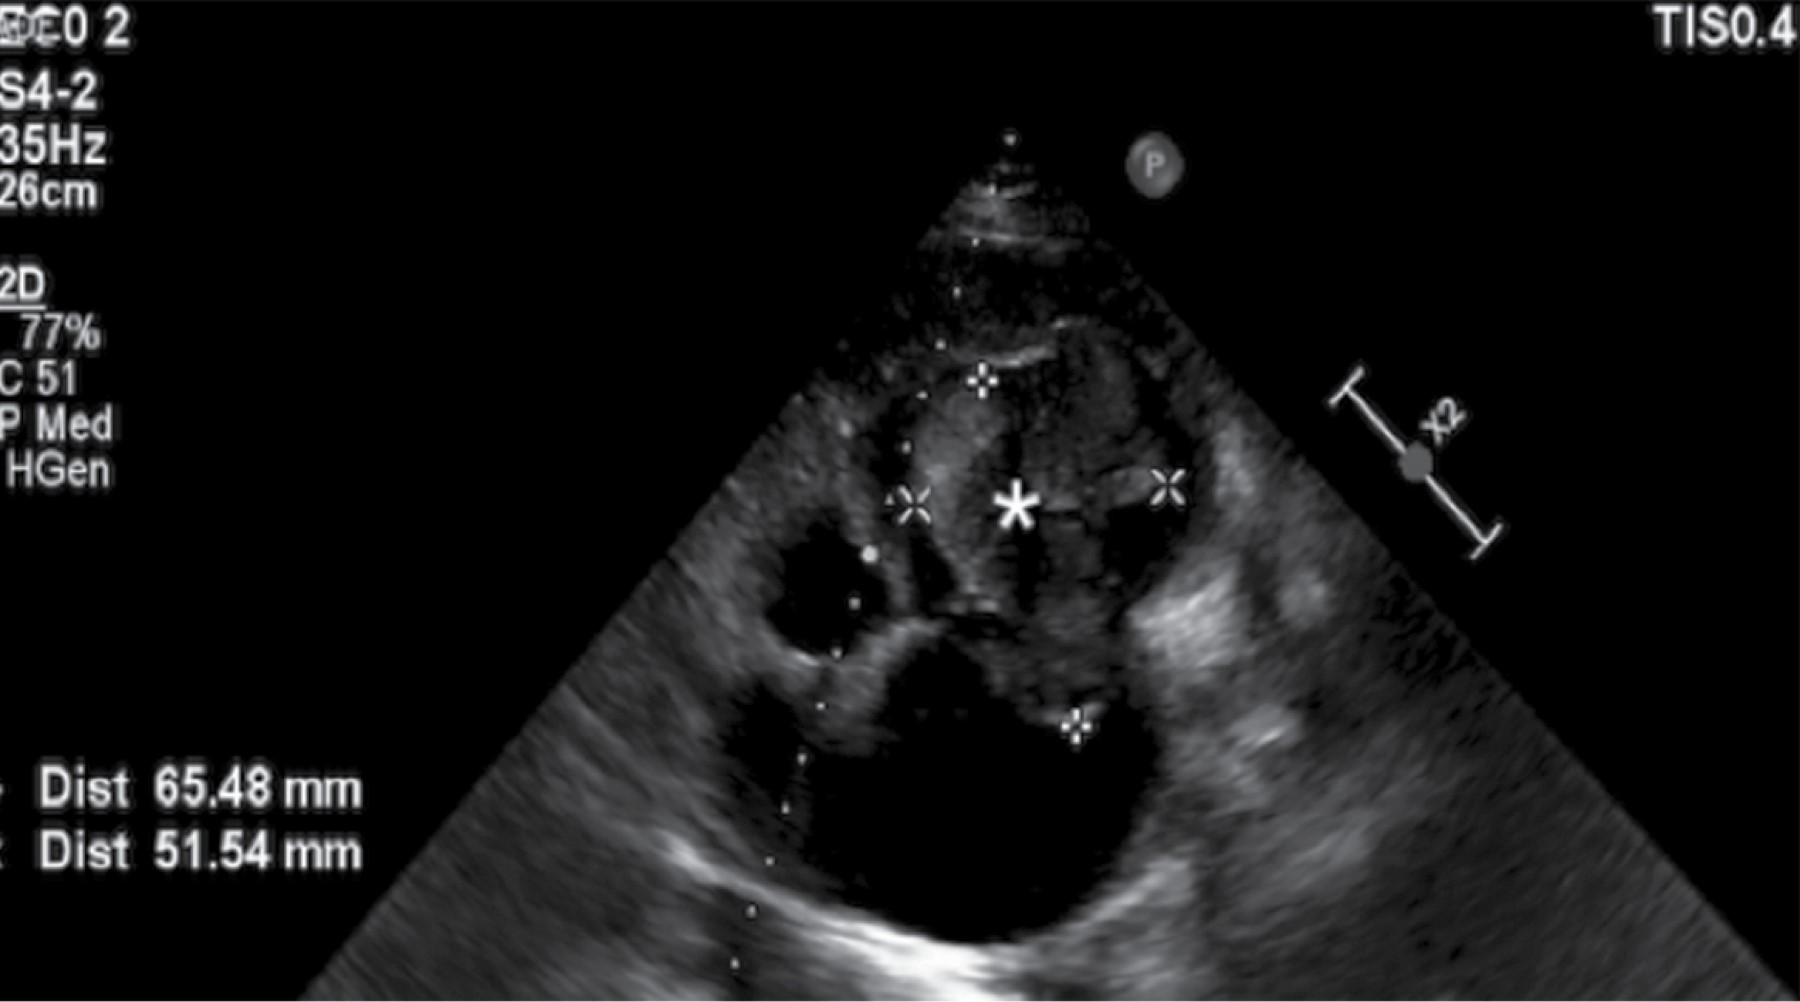

Enorme masa ventricular derecha en un paciente masculino de 25 años

Un joven varón acudió al Servicio de Urgencias del Hospital Santa Marcelina de Cidade Tiradentes con signos de insuficiencia cardíaca congestiva y pérdida de apetito. Se realizó un ecocardiograma bidimensional y se detectó una enorme masa ventricular derecha. Las masas cardíacas son siempre un desafío, y este artículo proporciona una revisión sobre el tema.

Figura 2